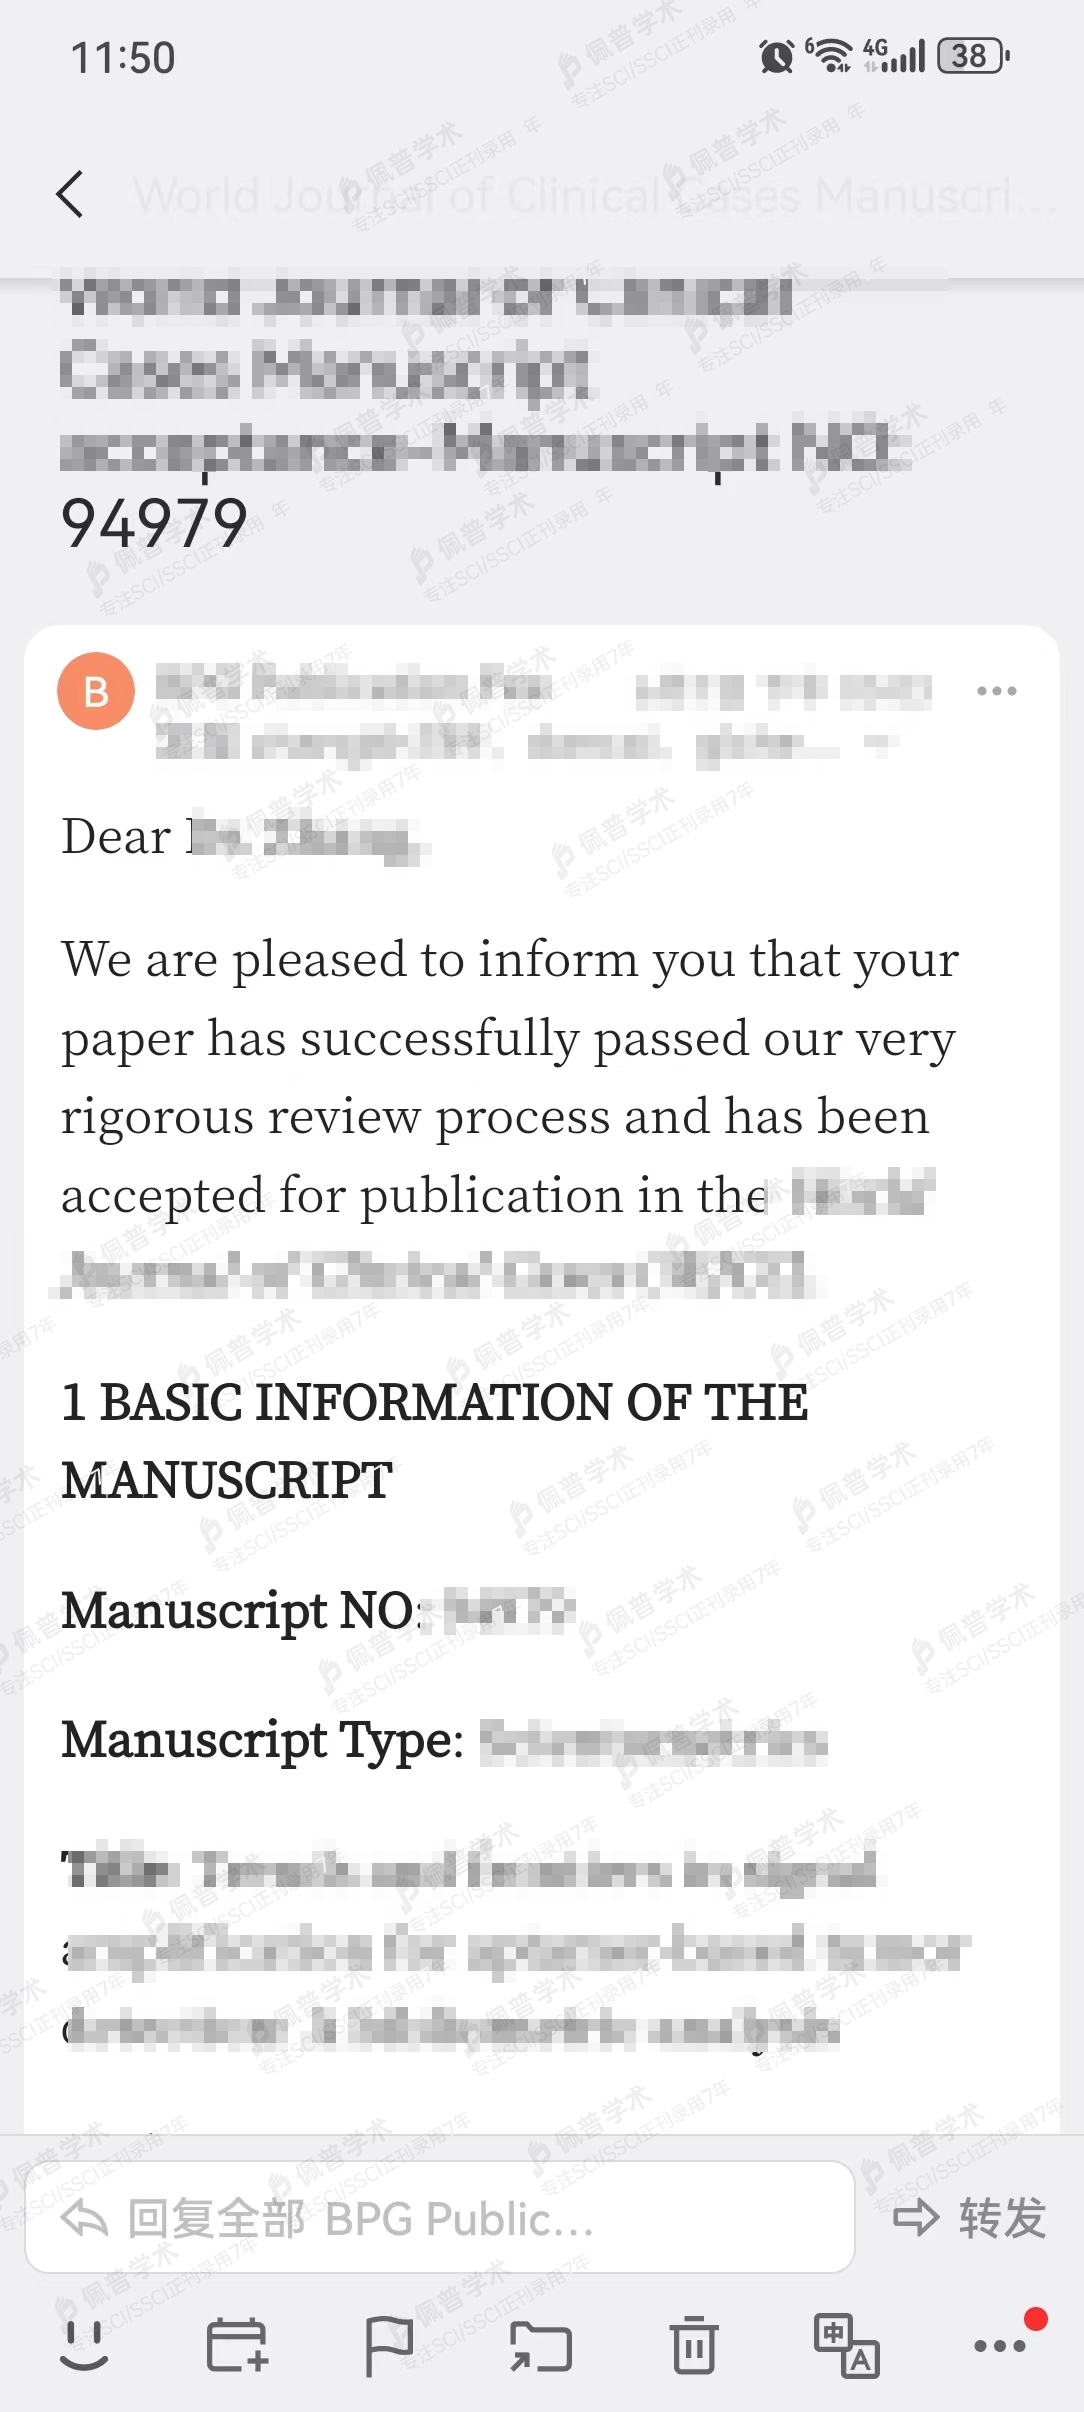

接收函展示